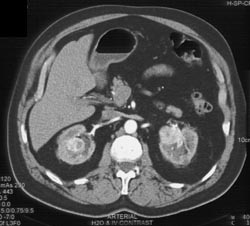

Hematoma S/P Nephrectomy